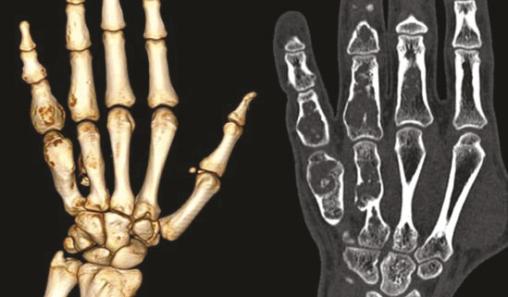

La radiographie standard met en évidence de multiples lésions osseuses lytiques métaphyso-diaphysaires géographiques, avec une fine ostéosclérose périphérique de type Ia de Lodwick, au niveau des métacarpes et des phalanges des 4e et 5e rayons de la main gauche. Ces lésions osseuses sont soufflantes, avec un discret amincissement des corticales (fig. 2 ). Une tomodensitométrie confirme les données de l’imagerie standard et ne montre pas de signes de transformation sarcomateuse (fig. 3 ). Les constatations cliniques et radiologiques permettent de poser le diagnostic de maladie d’Ollier.

La radiographie standard met en évidence de multiples lésions osseuses lytiques métaphyso-diaphysaires géographiques, avec une fine ostéosclérose périphérique de type Ia de Lodwick, au niveau des métacarpes et des phalanges des 4e et 5e rayons de la main gauche. Ces lésions osseuses sont soufflantes, avec un discret amincissement des corticales (